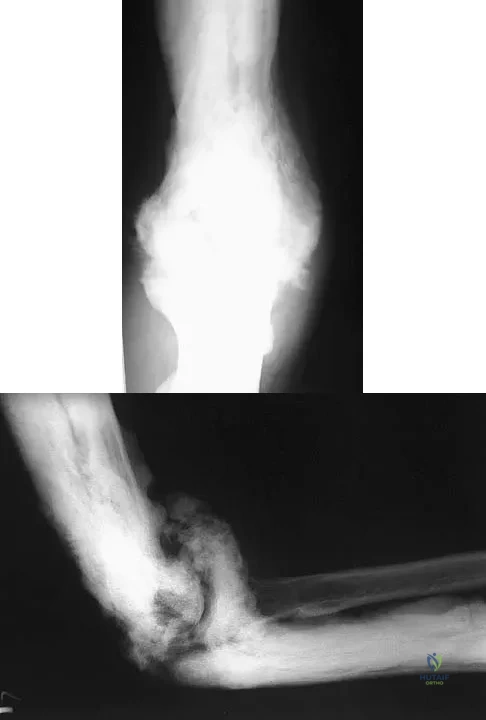

Question 86

A 35-year-old man has atraumatic painless limited elbow motion. Radiographs are shown in Figures 33a and 33b. What is the most likely diagnosis?

Explanation